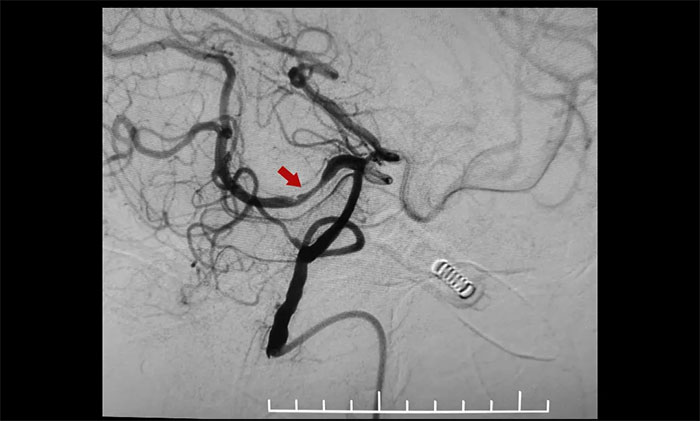

患者為老年男性,因腦梗加重入院。腦血管造影顯示,右側(cè)大腦中動脈M1段閉塞、右側(cè)大腦后動脈P1、P2交界段重度狹窄。并且,患者血管條件差、迂曲明顯、責任血管纖細,手術(shù)極其容易出現(xiàn)出血,局部血栓形成等風險,手術(shù)難度不言而喻。

術(shù)中,通過輸送型球囊擴張微導管輕松越過狹窄病變,完成右側(cè)大腦后動脈狹窄段的球囊擴張及支架置入等步驟,無需進行微導管交換、球囊交換以及支架微導管交換的過程。手術(shù)治療部分僅耗時30分鐘。術(shù)后造影顯示右側(cè)大腦后動脈P1、P2交界段重度狹窄明顯改善。行支架CT見支架成形良好。

▲ 術(shù)前,右側(cè)大腦后動脈重度狹窄